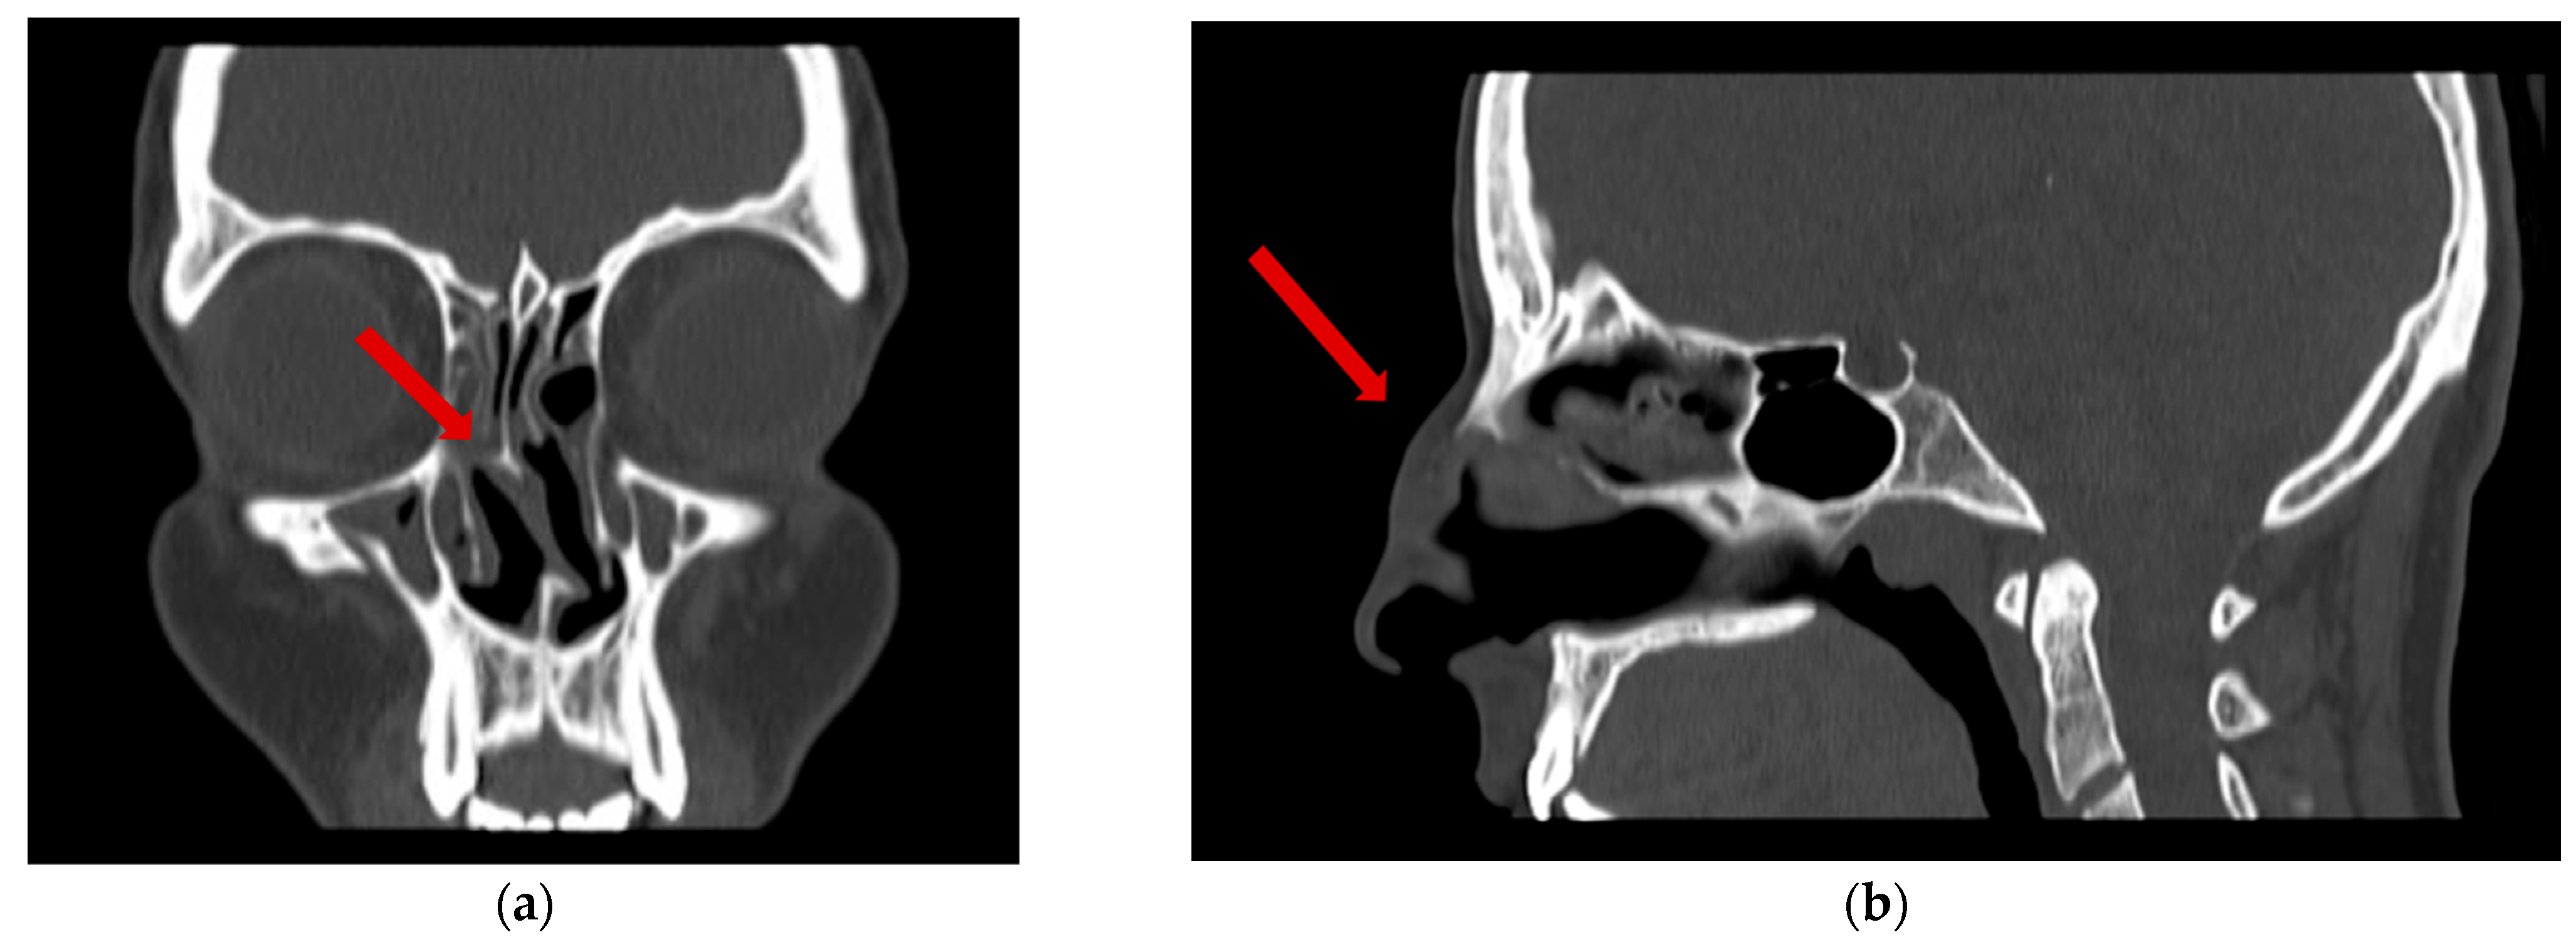

2.2. Investigations